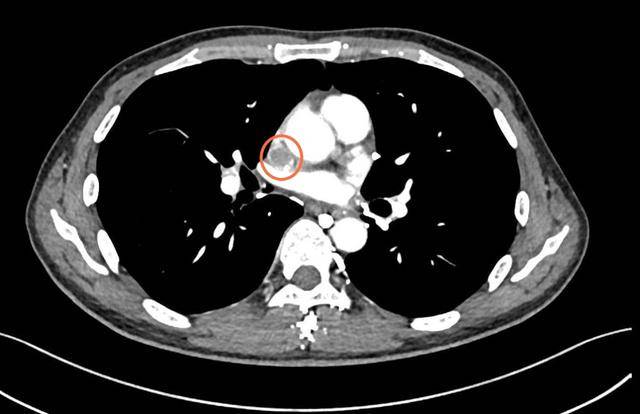

肿瘤刚被“摘”下来,心脏及大血管外科梁凯团队立刻接力,精准切除被肿瘤侵犯的上腔静脉病变段,并把一段14厘米长的特制人工血管,接到剩余的上腔静脉上,重新打通上半身回血的“高速公路”。

4小时后,手术顺利结束。术中出血控制良好,靳先生的生命体征平稳。术后没几天,靳先生胸闷、咽不下饭的症状消失,复查结果显示:肿瘤切除彻底,人工血管通畅,血流恢复良好。